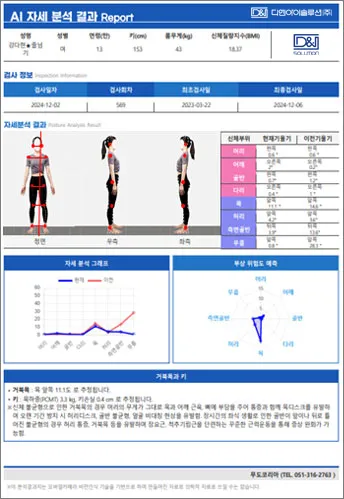

신체 부위별 불균형, 현재 체형의 불균형을 방치했을 경우 예상되는 미래 체형 정보, 신체밸 런스 지 수까지 분석리포트 제공

정면, 측면으로 분석하여 인체 근골격 모델로 현재의 신체 불균형 분석과 미래 체형을 예측

분석항목 : 거북목, 얼굴비대칭, 어깨불균형, 골반전·후방경사, 신체균형점, 내반슬(O다리), 외반슬(X다리), 반장슬(백니) 등

효과적인 체형 교정을 위한 AI 알고리즘의 신체 불균형 분석